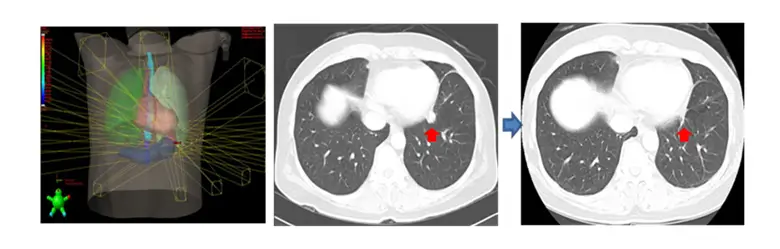

호흡동기 방사선치료 (Respiratory-Gated Radiation Therapy)

호흡주기 맞춤형 4차원 CT 영상을 이용하여 치료 계획을 만들고 치료에 응용하는 호흡동기방사선치료 (Respiratory-gated Radiation Therapy)를 시행하고 있습니다. 방사선치료 중 환자는 평소와 같이 편안하게 호흡을 하고 있으면, 영상장치를 이용하여 종양이 가장 적게 움직이는 호흡주기에만 선택적으로 방사선을 치료하는 방법입니다.